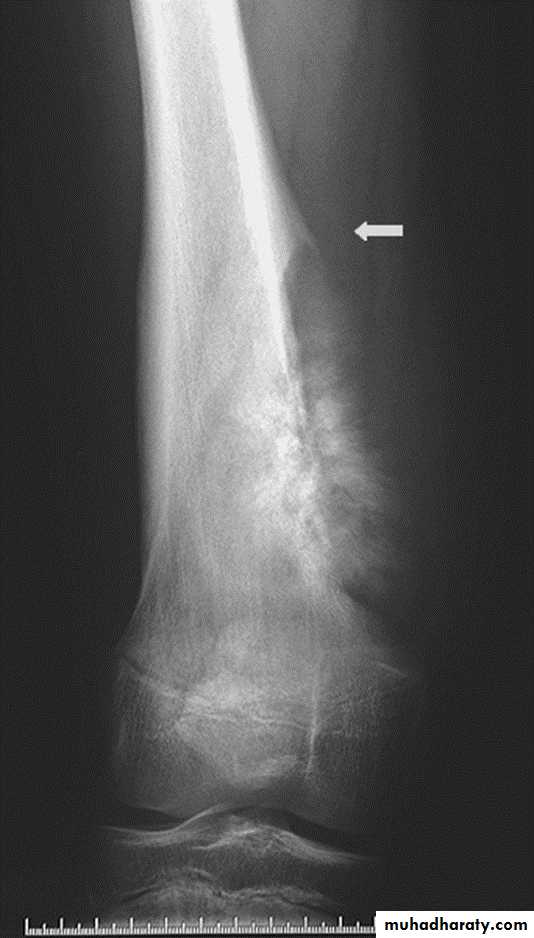

Ewings Sarcoma

Highly malignant with tendency to metastasize.Age: children.

Site: shaft of long bone.

Findings:

ill-defined destruction with onion peal periosteal reaction.

Ewing's sarcoma. Sunray speculation Onion peel appearance